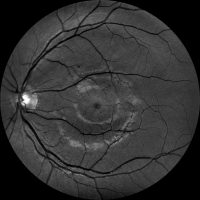

Dzięki technologi SLO – Scanning Laser Ophthalmoscope, podczerwieni oraz wiązki zielonego laseru, jesteśmy wstanie wykonać bardzo dokładny zrzut dna oka, dzięki czemu wykryjemy praktycznie każde zmiany w gałce ocznej. W realizacji takiego skanu nie potrzebne jest zakroplenie oka co znacznie usprawnia nam diagnostykę pod katem szybkości badania czy samopoczucia osoby poddanej tejże czynności. Badanie ma na celu wykrycie zmian w oku jak: jaskra, zaćma, zatory żylne, męty, retinopatie cukrzycową czy AMD(zwyrodnienie plamki żółtej), Pełna wizyta obejmuje: